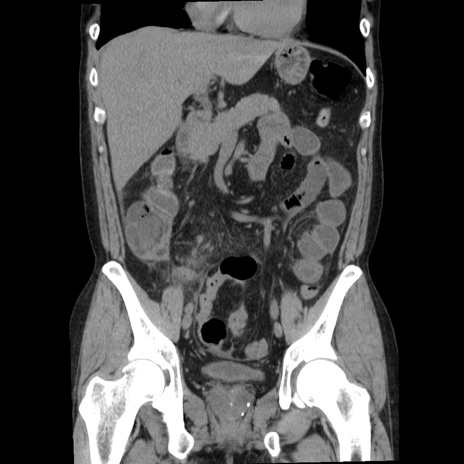

横断像

【症例】40歳代男性

【現病歴】2日前から胃痛あり。徐々に周期的な激痛に変化した。本日になっても激痛があるため受診。

【身体所見】意識清明、BT 38-39℃台あり、腹部:膨満、やや硬、右下腹部に圧痛あり。

【データ】WBC 8500、CRP 23.26